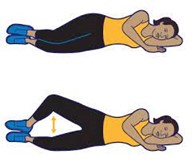

- حرکت کلمز (clamshell exercise) (تصویر شماره۱۷ ) :

این تمرین عضلات مختلفی اعم از عضلات ابداکتور(ماهیچههای نزدیککننده ران) و عضلات باسن را درگیر میکند.

جهت اجرای حرکت کلمز باید:

رو به پهلوی چپ دراز بکشید و باسن و پاها را در یک راستا نگه دارید.

زانوها را ۴۵ درجه خم کنید و به آرامی و بدون اینکه کمر یا لگن حرکت کند، زانوی بالایی را تا جایی که میتوانید بالا ببرید.

سپس به آرامی زانویتان را پایین بیاورید و به وضعیت اولیه برگردانید.

(تصویر شماره۱۷ )